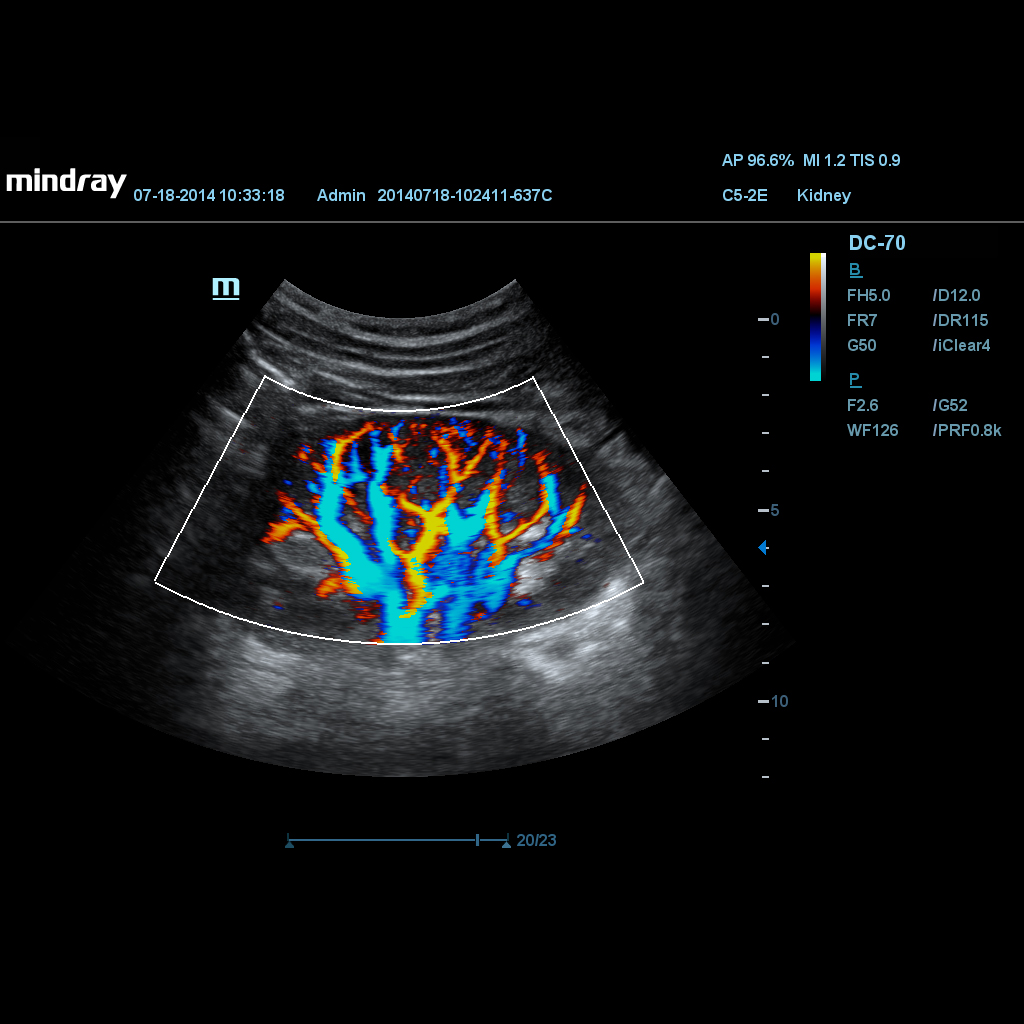

HDR Flow (High Dynamic Range Flow)